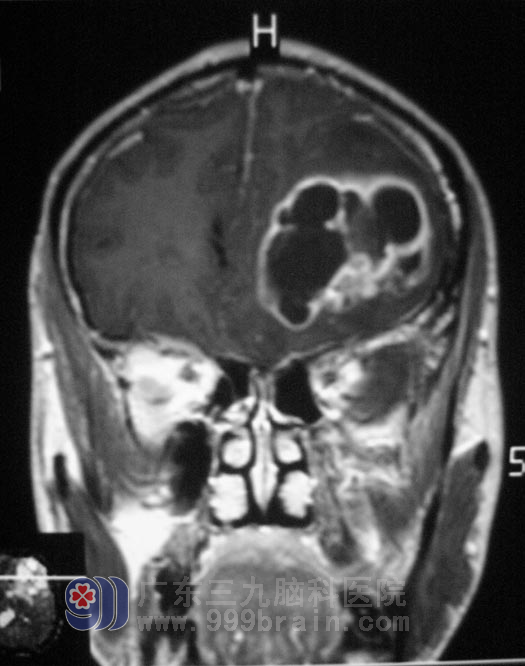

今年4月中旬,广东三九脑科医院的MR检查结果证实了家人的猜测:“左侧额叶、岛叶囊实性占位,内有少量出血,占位周围边界不清,水肿严重,初步考虑为胶质瘤”。http://www.999brain.com/

4月22日龙大爷再次来到广东三九脑科医院,医生告诉龙大爷脑部占位周围水肿厉害,肿瘤内有出血,如果不手术治疗,病人生命随时会受到威胁。

手术前